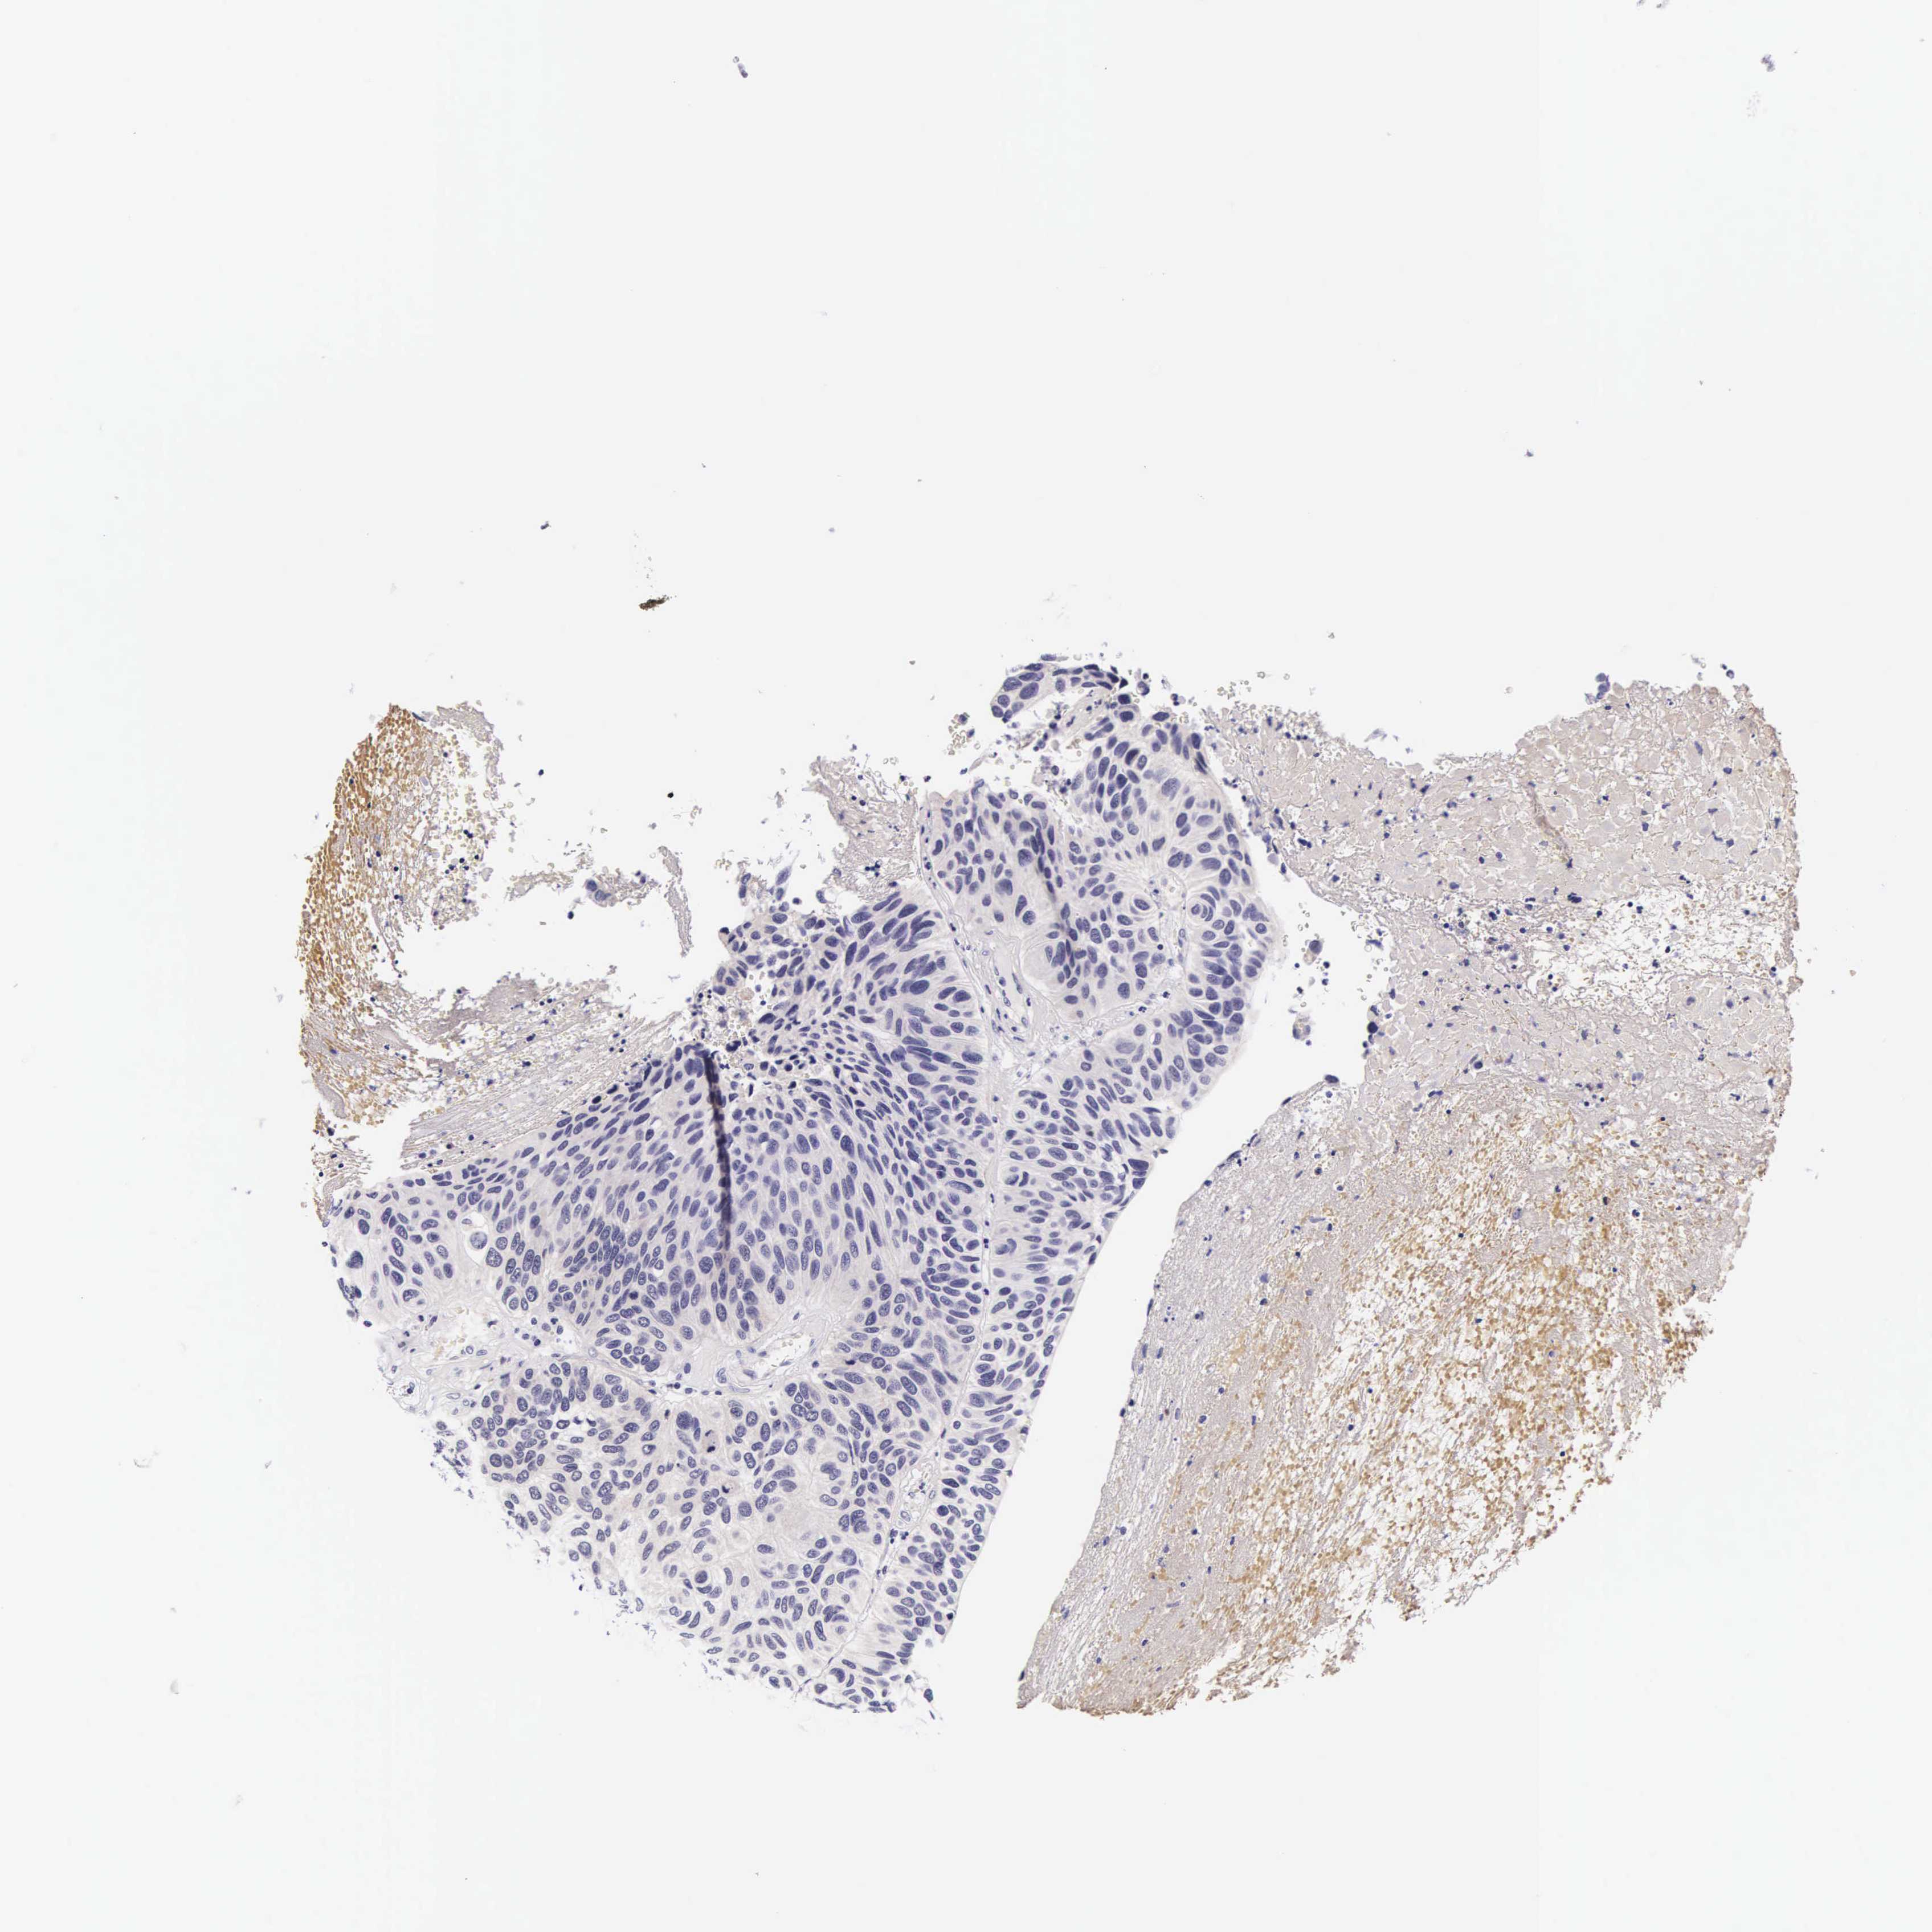

UROTHELIAL CANCER - Protein expressioni

A mouse-over function shows sample information and annotation data. Click on an image to view it in a full screen mode. Samples can be filtered based on level of antibody staining by selecting one or several of the following categories: high, medium, low and not detected. The assay and annotation is described here.

Note that samples used for immunohistochemistry by the Human Protein Atlas do not correspond to samples in the TCGA dataset.

Antibody stainingi

Antibody staining in the annotated cell types in the current human tissue is reported as not detected, low, medium, or high, based on conventional immunohistochemistry profiling in selected tissues. This score is based on the combination of the staining intensity and fraction of stained cells.

Each image is clickable and will lead to virtual microscopy that enables deeper exploration of all samples and also displays staining intensity scores, fraction scores and subcellular localization as well as patient and tissue information for each sample.

Antibody HPA000647

Staining

High

Medium

Low

Not detected

Intensity

Strong

Moderate

Weak

Negative

Quantity

>75%

75%-25%

<25%

None

Location

Nuclear

Cytoplasmic/membranous

Cytoplasmic/membranous,nuclear

Urothelial carcinoma, High grade

Urothelial carcinoma, Low grade